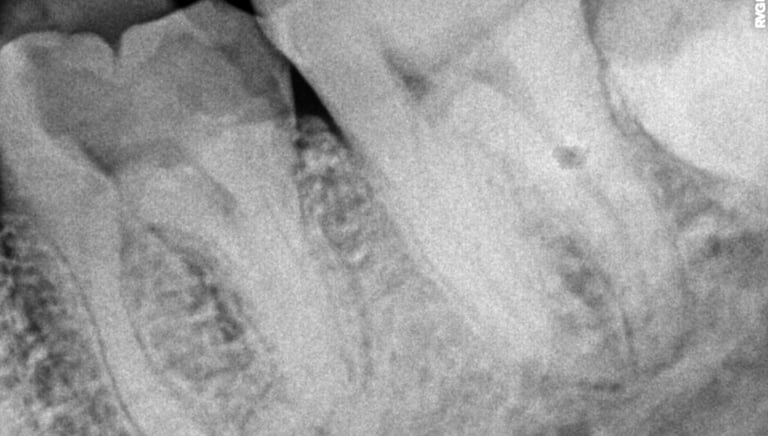

Root Canal Treatment near Shyamal, Ahmedabad

All images shown here represent real clinical cases treated at our dental clinic with patient consent.

At Shree Dental Care, we focus on gentle, precise, and well-planned root canal treatment to remove infection, relieve pain, and preserve your natural tooth structure.

Patients from Shyamal and nearby areas of Ahmedabad visit our clinic for comfortable root canal procedures carried out using modern techniques and strict hygiene protocols. The treatment helps eliminate infection from inside the tooth, prevents further damage, and restores normal chewing function.

Thorough clinical examination and digital X-rays.